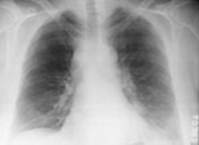

La radiographie pulmonaire montre un élargissement du médiastin lié à des adénopathies. On ne retrouve pas d’atteinte du parenchyme pulmonaire.

Figure 3 : Radiographie thoracique montrant un élargissement du médiastin et un petit épanchement pleural gauche (19).